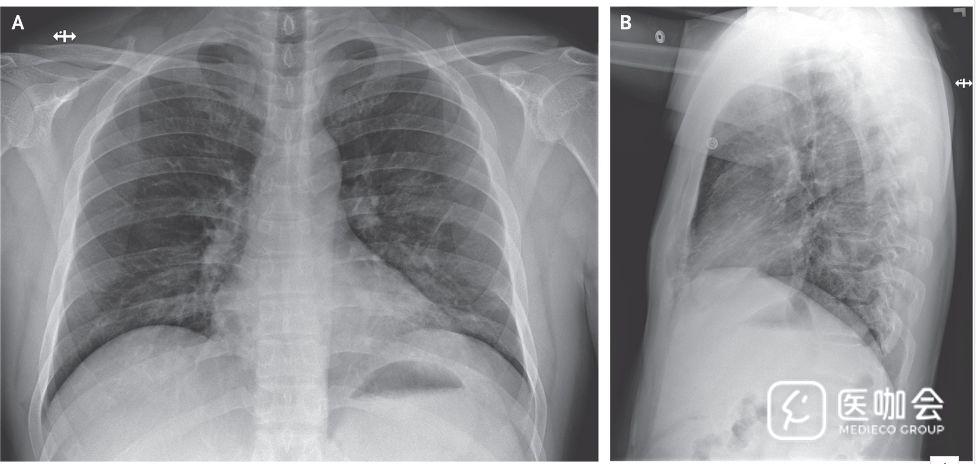

除了有高甘油三酯血症病史外,患者身体健康,且不吸烟。体格检查显示患者体温37.2°C,血压134/87mmHg,脉搏110次/分,呼吸频率16次/分,氧饱和度96%。肺部听诊显示干啰音,胸片无异常(图1)。

图1. 患者胸片

患者住院第3天(患病第7天)时,胸片仍未显示浸润或异常表现(图3)。但是,在住院第5天(患病第9天)晚上的胸片显示,左肺下叶有肺炎表现(图4)。

图3. 患者住院第3天(患病第7天)的胸片